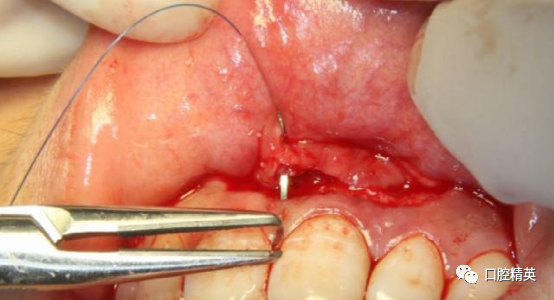

上方覆盖PRF膜3-5份。完全覆盖骨缺损,减张缝合。

唇系带处理后做第一缝合位点,梯形边角区做第二第三缝合位点。

缝合完成。塞治剂塞治,局部加压。